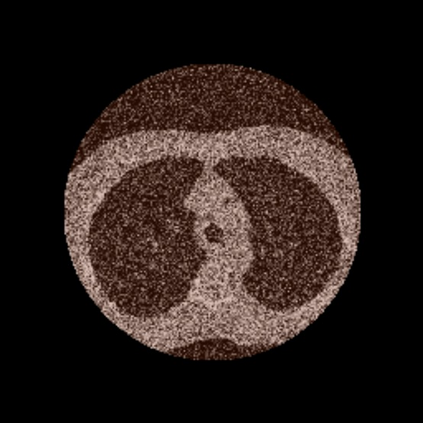

Anatomically consistent field-of-view (FOV) completion to recover truncated body sections has important applications in quantitative analyses of computed tomography (CT) with limited FOV. Existing solution based on conditional generative models relies on the fidelity of synthetic truncation patterns at training phase, which poses limitations for the generalizability of the method to potential unknown types of truncation. In this study, we evaluate a zero-shot method based on a pretrained unconditional generative diffusion prior, where truncation pattern with arbitrary forms can be specified at inference phase. In evaluation on simulated chest CT slices with synthetic FOV truncation, the method is capable of recovering anatomically consistent body sections and subcutaneous adipose tissue measurement error caused by FOV truncation. However, the correction accuracy is inferior to the conditionally trained counterpart.